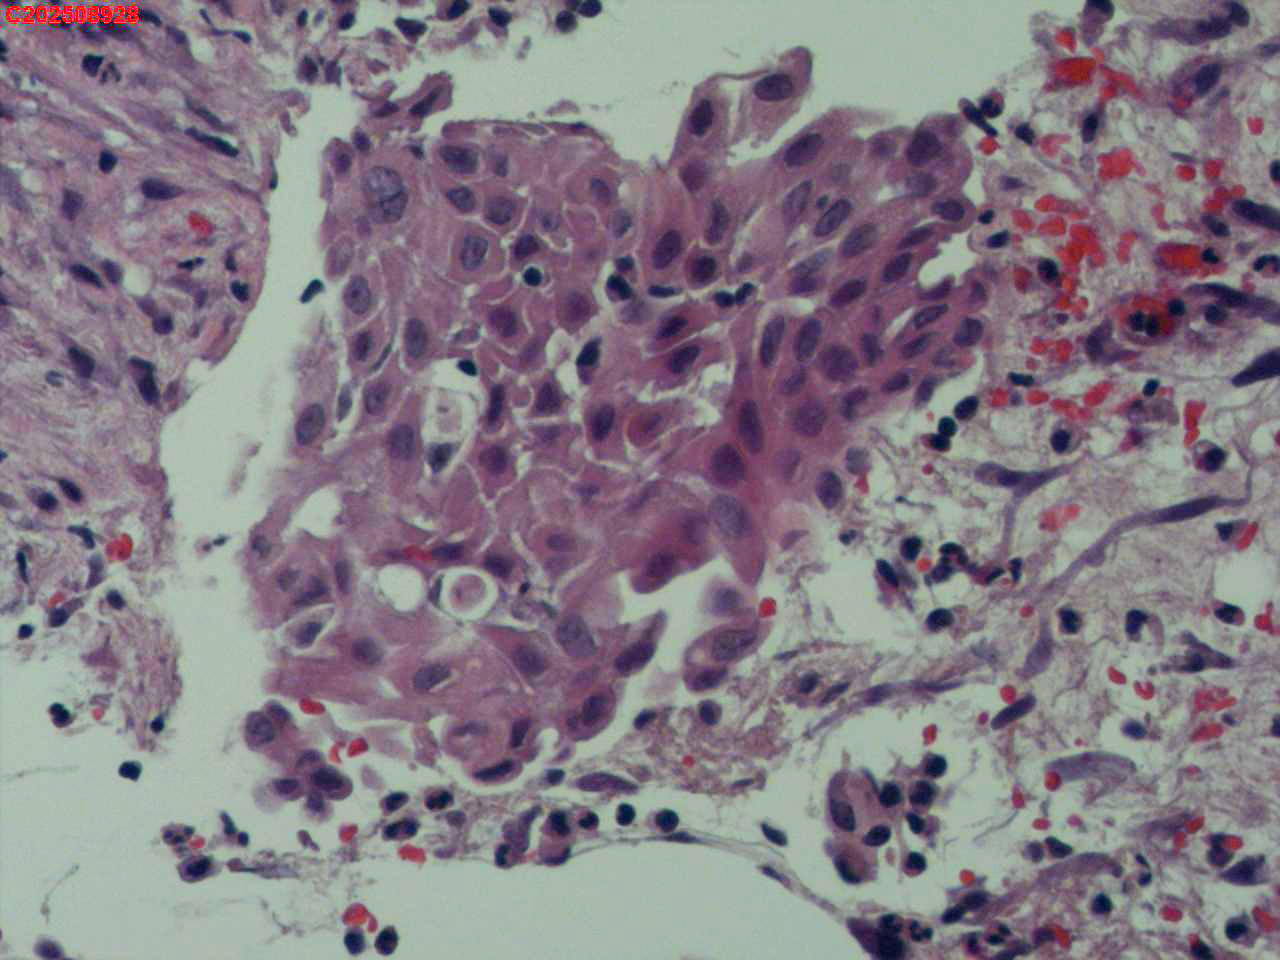

喉部右侧、声带下方咬检

男

56岁

喉Ca?

咳嗽

喉室内右侧声带下方新生物。

考虑鳞癌

鳞癌,有微浸润